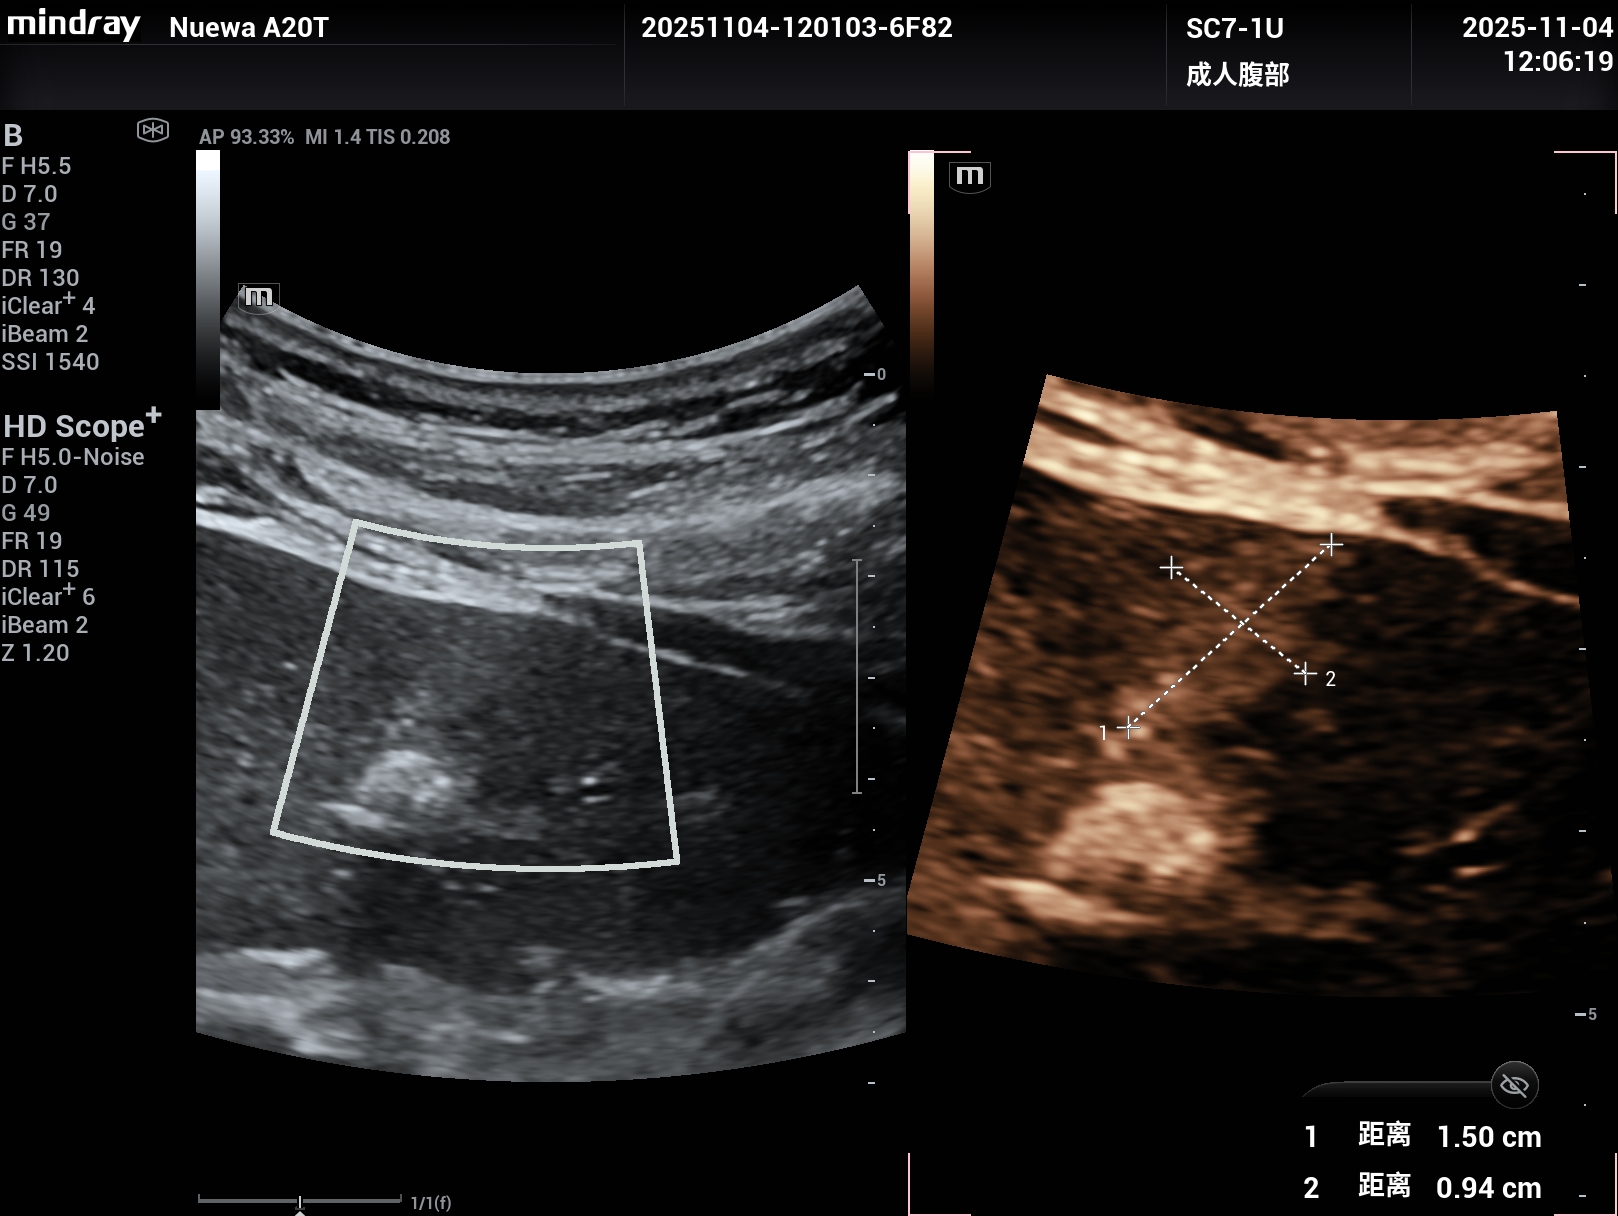

睿瞳技术,是具有独立的发射和接收电路设计的成像技术,组织回声信息更多,图像信息更丰富。

上2幅图是采用了Nuewa A20睿瞳技术的图片,下2幅是没有采用睿瞳技术的图片。